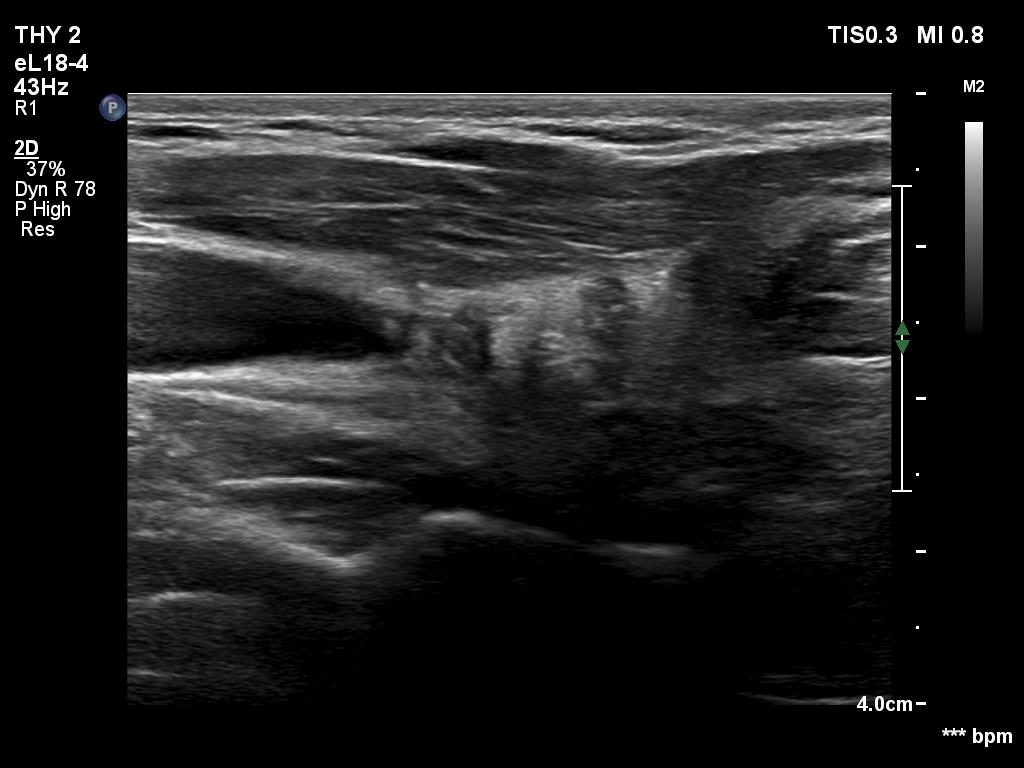

First examination (1st to third rows of images):

Clinical data: A 14-year-old boy was referred for evaluation of a nodule discovered by himself.

Palpation: a hard, not freely moveable nodule in the isthmic part of the left lobe.

Ultrasonography revealed a hypoechogenic nodule in the ventromedial part of the left lobe. The nodule had irregular borders, contained microcalcifications and displayed perinodular and irregular intranodular blood flow.